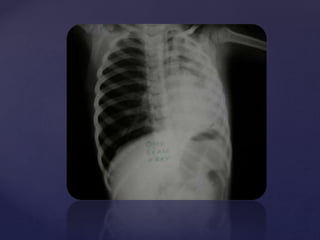

 Plain X Ray neck ,

chest and abdomen

AP view.

 Showing a round

radio opaque foreign

body in the

esophagus.

 Probably a coin.

Fig 2

 Plain X Ray neck

Lateral view.

 Showing edge on

view in lateral view

suggesting of FB in

oesophagus (in

contrast to FB

trachea)